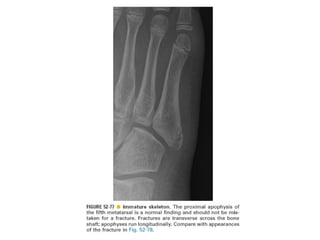

Skeletal trauma was presented by Dr Laith Fadhel with reference to Grainger's Diagnostic Radiology textbook. The presentation covered skeletal trauma as assessed through diagnostic radiology techniques. Key findings and treatments for skeletal injuries were likely discussed.